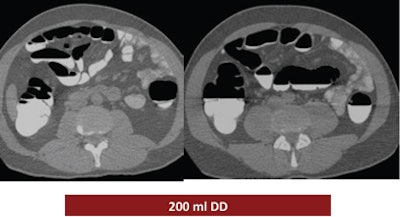

The study looked at three groups of 30 patients who underwent virtual colonoscopy after a same-day bowel preparation. Group 1 ingested 200 mL of undiluted DD the day of the exam, group 2 drank 100 mL of the agent the day of the exam, and group 3 ingested a low-dose polyethylene glycol (PEG) formula (macrogol) the two days before the exam, followed by 100 mL of DD the day of the exam.

| Above, the use of 200 mL DD in group 1 yielded the highest quality scores. While the colonic mucosa was well marked, significant volumes of fluid remained in the colon, similar to the 100 mL DD preparation (group 2, below). The use of 100 mL combined with low-dose polyethylene glycol over two days (bottom image) may have improved fecal tagging by softening the stool before the ingestion of DD. |